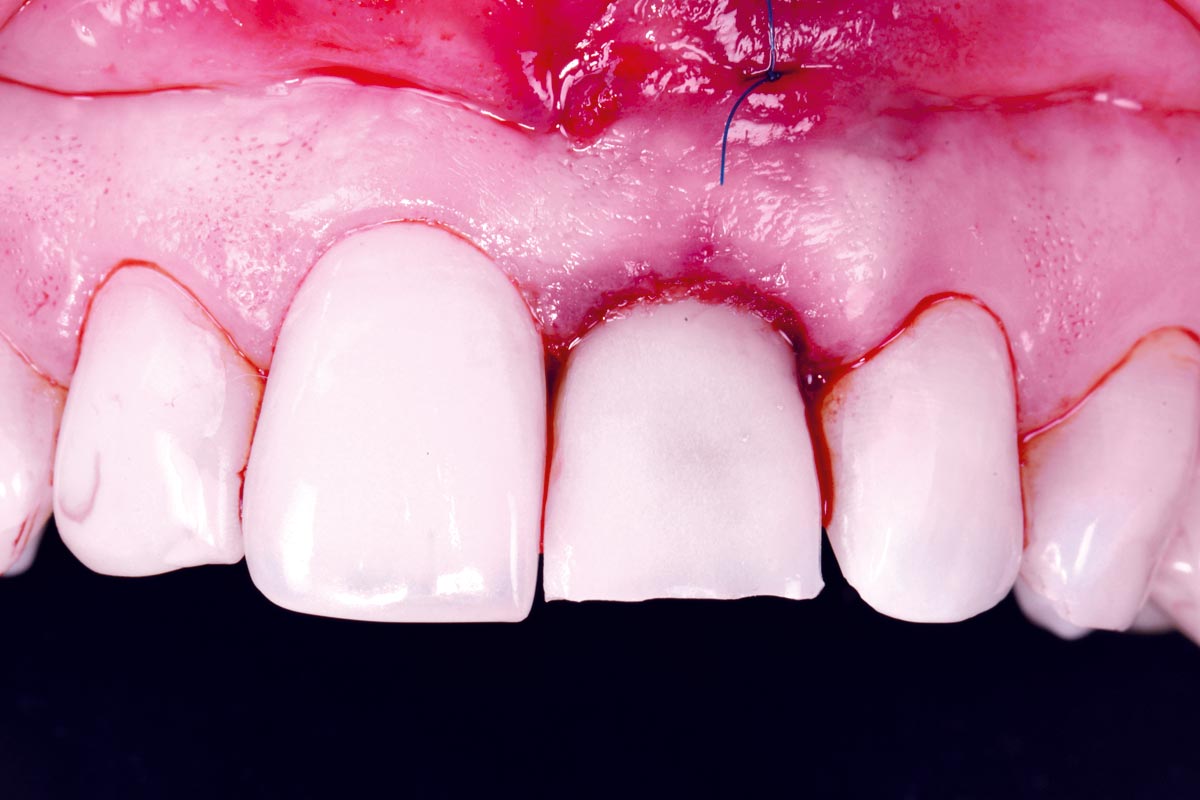

Excellent aesthetic result of buccal augmentation with mucoderm® and maxgraft® after immediate implant placement - 3-years follow-up - Dr. A. Puišys

Initial view of the case. Discoloration of 1.1 and mild class I gingival recession